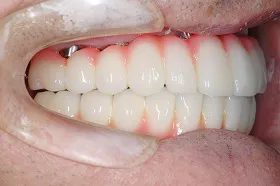

■治療後:上下顎 複数本のインプラントを使い固定式で治療

| 主訴 | 現在義歯を使用しているが、しっかりと咬んでなんでもおいしく食事したい |

| 治療方法 | 上下顎 複数本のインプラントを使用しての治療 |

| 治療期間 | 約1年 |

| 通院回数等 | 約20回 |

| 費用 | 約600万円(税込) |

| リスク・副作用 | 術後の腫れ・痛み |